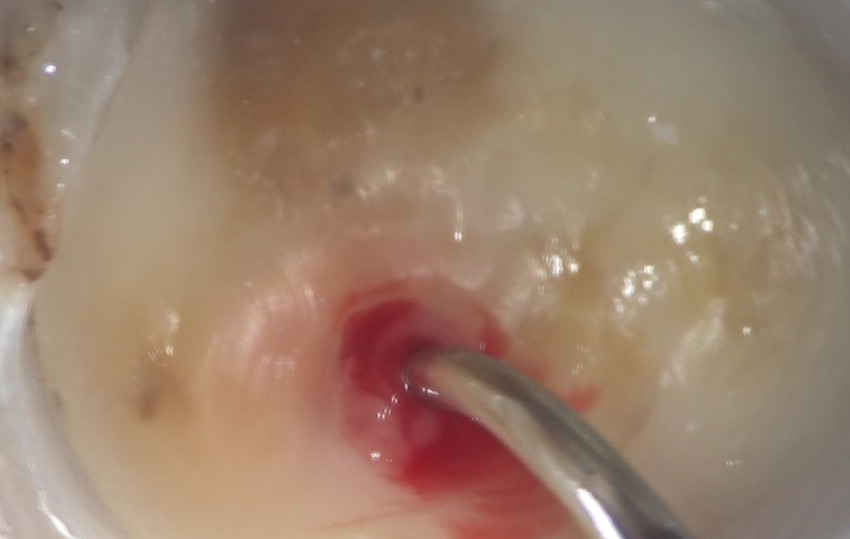

この神経を洗い流し、この軟組織の入っている部分のその上の部分取り除いた部分です。左右に見えるのが、神経の管、つまり根管の入り口です。

この後、この内部の入り込んでいるかもしれない細菌を取り除き、また、これ以上細菌感染しないように、処置をしていくのが根管治療です。